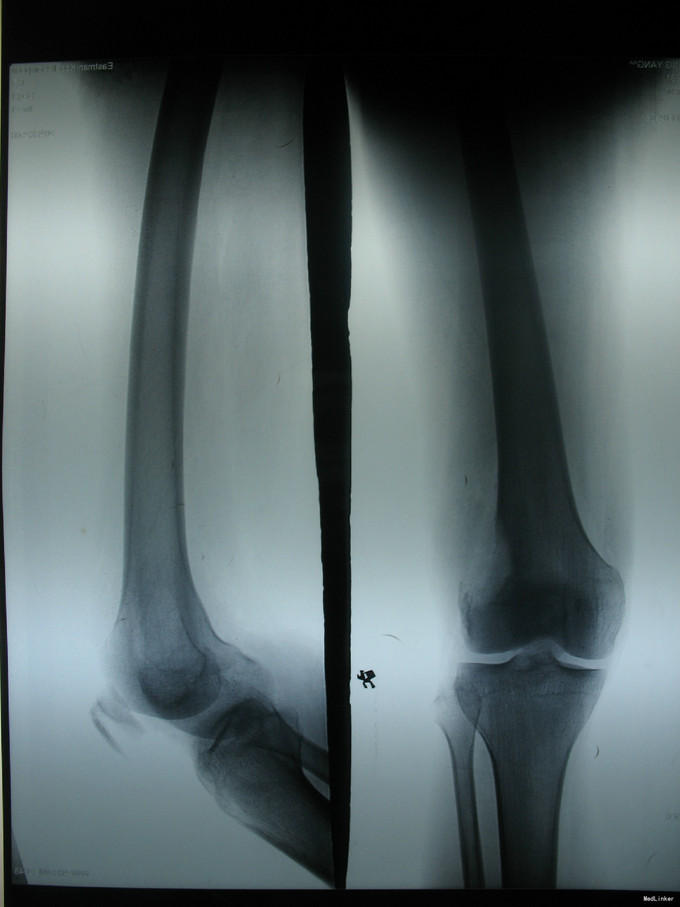

右膝上疼痛2个月肿胀一周 患者2个月前无明显诱因出现右膝上疼痛,逐渐加重,一周前活动后加重明显并开始出现肿胀,右膝关节活动受限,于当地医院行CT及MRI检查考虑为恶性肿瘤,遂来我院治疗。

右膝上股外侧肿胀明显,压痛(++),皮温略高,皮色正常,右膝关节屈伸活动明显受限。